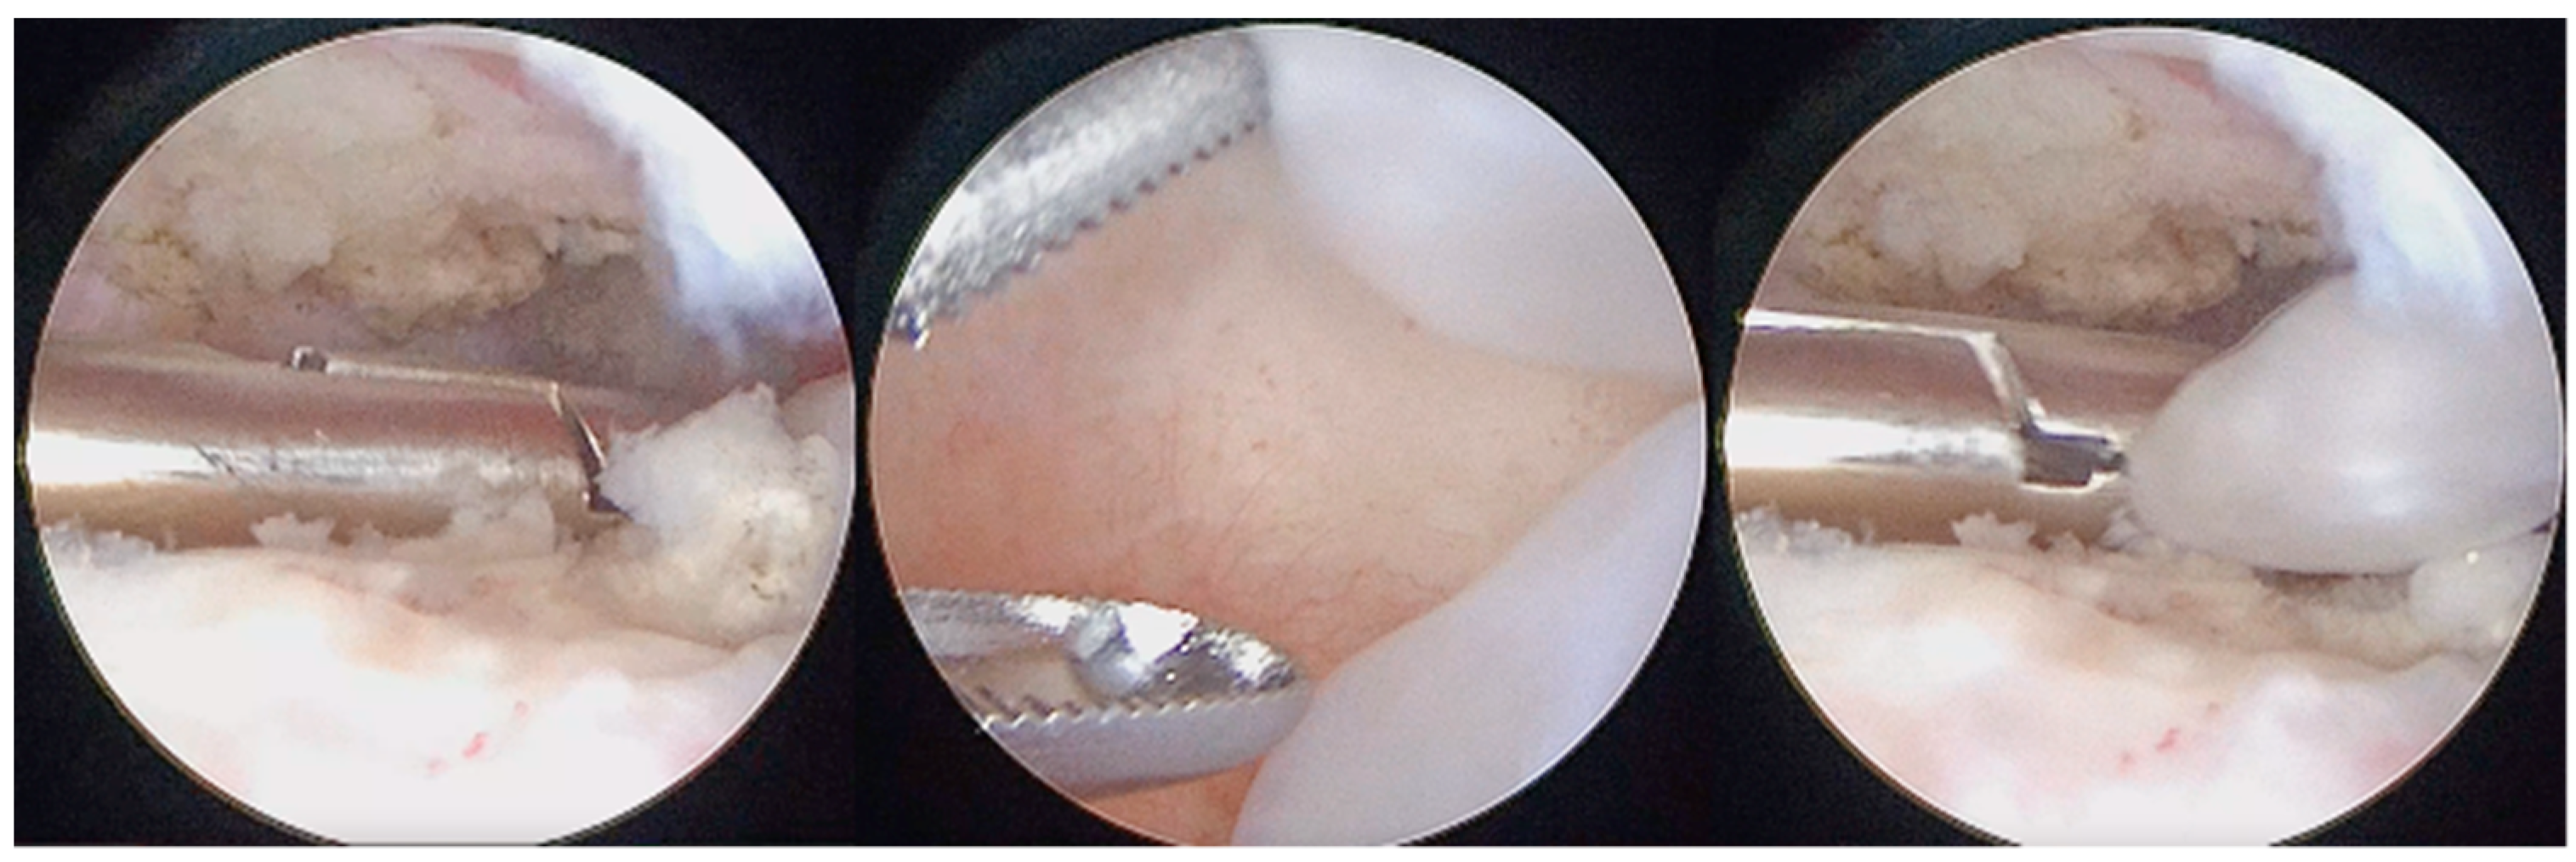

Figure 5.

Arthroscopic removal of LBs and synovial nodules using forceps.

Figure 6.

Coblation of metaplasic nodules and division of large LBs to ease their washout.

Figure 7.

Coblation treatment of the metaplasic synovia, performing the so-called selective synoviectomy.